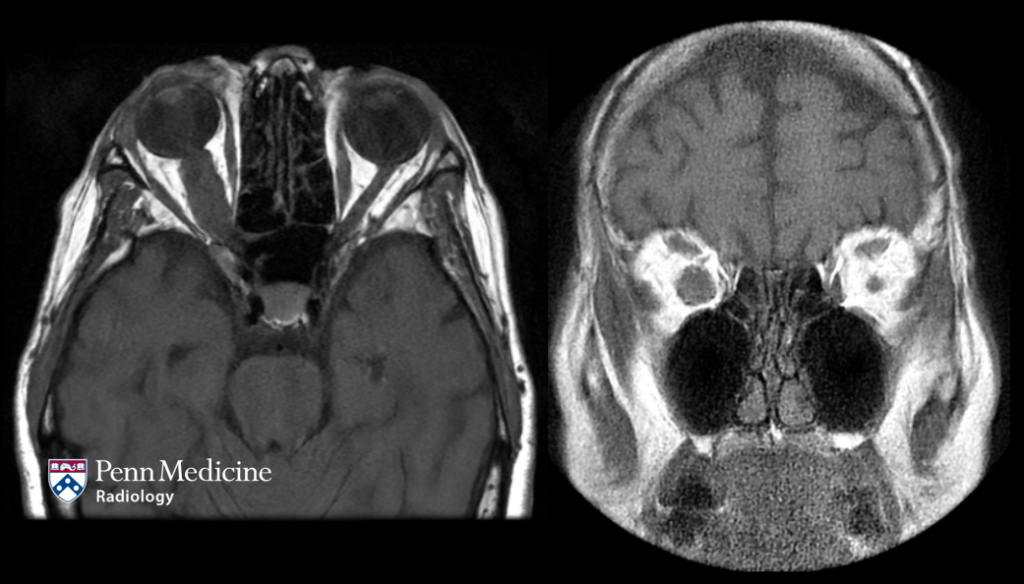

66-year-old man with history of chronic sinusitis

A 66-year-old man presented with chronic sinusitis.